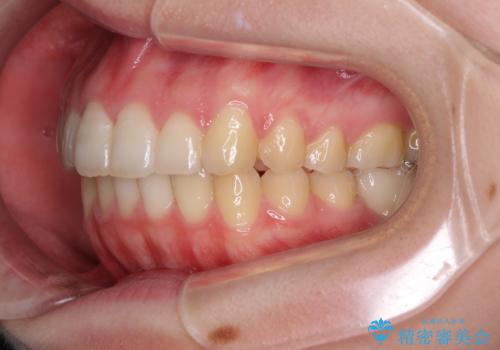

- 口の閉じにくさと割れてしまった奥歯を気にして来院された患者様です。

IPR(歯と歯の間を削る)と歯列全体の後方移動によって口元が引っ込むように設計し、インビザラインにより治療を行うこととしました。

割れてしまった奥歯は抜歯し、矯正治療中の良いタイミングでインプラントを埋入することとしました。

インプラントは、治療期間を短くすることが可能な、ストローマン社のSLActiveを使用することとしました。

上下正中がずれていたため、抜歯による矯正治療も検討しましたが、口元がそれほど突出していなかったため、非抜歯にて矯正することになりました。

その結果正中のズレは残りましたが、口を閉じたときの感覚や奥歯の咬み合わせには全く問題なく、患者様には大変満足していただきました。